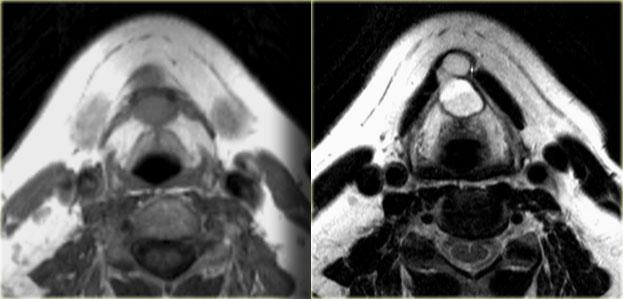

Bên trái là hình ảnh chuỗi xung T1W và T2W mặt phẳng ngang ở mức xương móng.

Không có ngấm thuốc tương phản từ trên chuỗi xung sau tiêm Gadolinium (không hiển thị).

Đây là tổn thương dạng nang ở đường giữa, một phần nằm ngoài và một phần nằm trong xương móng, thuộc khoang tạng.

Tổn thương nằm trong cơ dây đai.